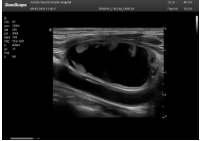

2相控陣探頭

探頭面是平面,接觸面小,近場(chǎng)視野最小,遠(yuǎn)場(chǎng)視野大,成像視野呈扇形,適用于心臟。

心臟探頭通常按應(yīng)用人群劃分為成人、兒童、新生兒三類:(1)成人心臟位置最深、搏動(dòng)速度慢;(2)新生兒心臟位置較淺、搏動(dòng)速度最快;(3)兒童心臟的情況介于新生兒與成人之間。

肥厚性心肌病-心尖四腔